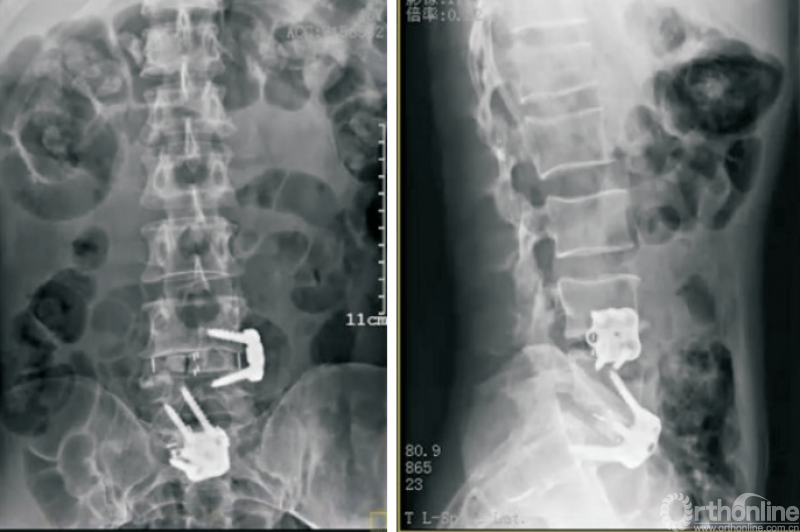

终板塌陷和融合器沉降(图6)是Stand-aloneOLIF的常见并发症,也是导致术后翻修的重要预测因素。融合器沉降与终板强度、手术操作以及解剖稳定性相关。终板硬化及形态平衡能够降低融合器沉降的发生率[36]。

图6 OLIF术后融合器沉降

LIU等[37]研究发现,在MRI影像中有Modic改变以及CT影像提示终板硬化的患者终板沉降的发生率明显低于其他患者。术中选择合适的融合器以及良好的脊柱稳定性也有利于降低融合器沉降的发生率[38]。ZHANG等[30]研究利用尸体标本模拟OLIF手术,通过研究生物力学特征、骨小梁微结构损伤等探索融合器与椎体骺环相对大小及位置对终板塌陷及融合器沉降发生率的影响,因此,在Stand-alone OLIF中选择合适的融合器对于减少终板塌陷及融合器沉降至关重要。

FANG等[39]通过构建有限元模型比较Stand-alone OLIF与OLIF联合后路钉棒系统固定两种手术方式后屈伸活动时终板应力等的变化,发现OLIF联合后路钉棒系统可降低屈伸活动时终板所承受的最大应力。术中终板损伤、间隙过度撑开等均会增大融合器沉降的发生风险。

因此,侧方钢板的应用能部分解决这个问题[43]。斜外侧脊柱融合固定系统(PIVOX)(图7)是目前比较成熟的侧方固定方式,已在我科初步应用,用于腰椎节段性不稳定、腰椎椎管狭窄、腰椎侧弯、腰椎盘源性腰痛、邻椎病(图7)等腰椎疾病,截至目前随访结果满意。

图7 PIVOX系统用于邻椎病

初步统计结果显示,相较于经典的OLIF组,PIVOX组并未明显增加融合器沉降、终板塌陷等并发症的发生率。在发挥Stand-alone OLIF优势的同时,保证了脊柱生物力学的稳定性,拓展了Stand-alone OLIF的应用边界。但是,NAYAK等[44]的研究发现,对于侧方脊柱融合术,后路螺钉固定的生物力学稳定性强于侧方钢板固定,因此,当需要刚性、消除运动的稳定时,仍然建议首选后路螺钉固定。